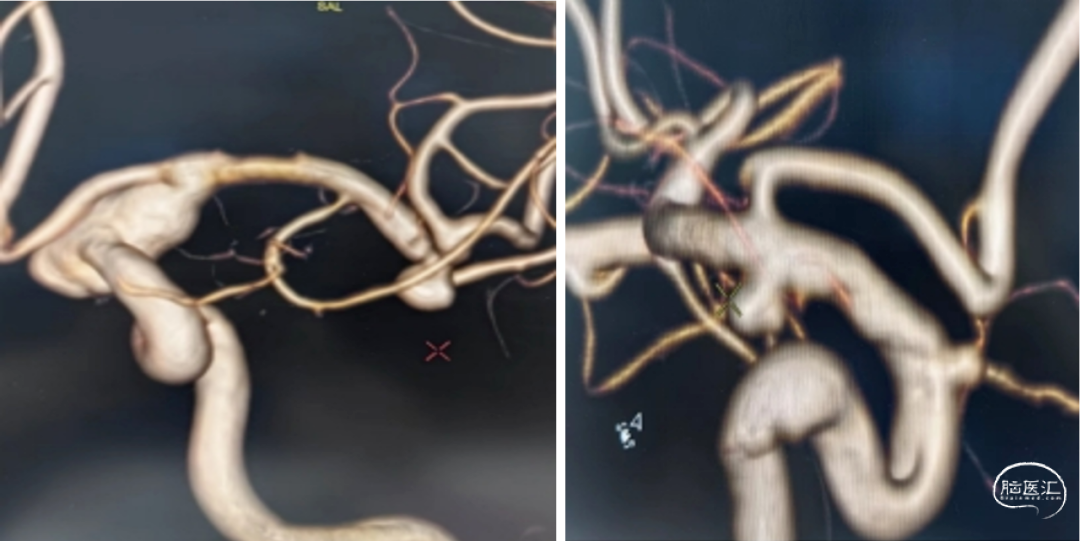

3D重建:

左侧颈内动脉末端夹层动脉瘤、左侧大脑中动脉分叉部动脉瘤、右侧颈内动脉脉络膜前动脉处动脉瘤。

a.左侧颈内动脉末端夹层动脉瘤形状不规则且囊体较大,大脑中分叉部动脉瘤有一分支发出,这两处动脉瘤相对危险性高,此次优先处理;右侧脉前动脉瘤二期治疗。

b.左侧颈内动脉末端夹层动脉瘤呈不规则长条形改变,脉络膜前动脉在瘤体远端发出,若选用传统的弹簧圈栓塞治疗,则有可能出现分支闭塞,引起并发症,因此考虑使用血流导向装置密网支架覆盖载瘤动脉,避免出现分支血管闭塞。

术前测量左侧颈内动脉末端夹层动脉瘤长10mm,瘤体最宽处8mm,载瘤动脉近端血管直径约4.2mm,远端血管直径约3.5mm。拟选用Nuva®血流导向密网支架 TJED-D-4.5-30(预期血管直径长度:4.0mm*40mm)。